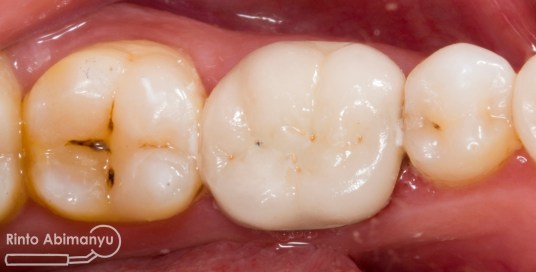

Setelah saya liat keadaan klinisnya ini yang saya lihat…

Gigi 46 terlihat kavitas masih ada karies yang sangat luas dan ada spot sudah terjadi tembus ke kamar pulpa.